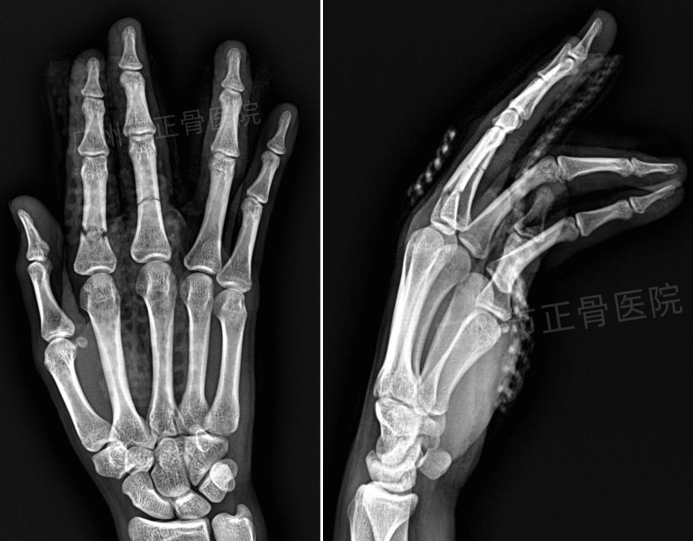

X线检查提示:“右手食指、中指近节中段骨折,骨折远端均向背侧移位,向掌侧成角。”

▲复位前,骨折成角移位